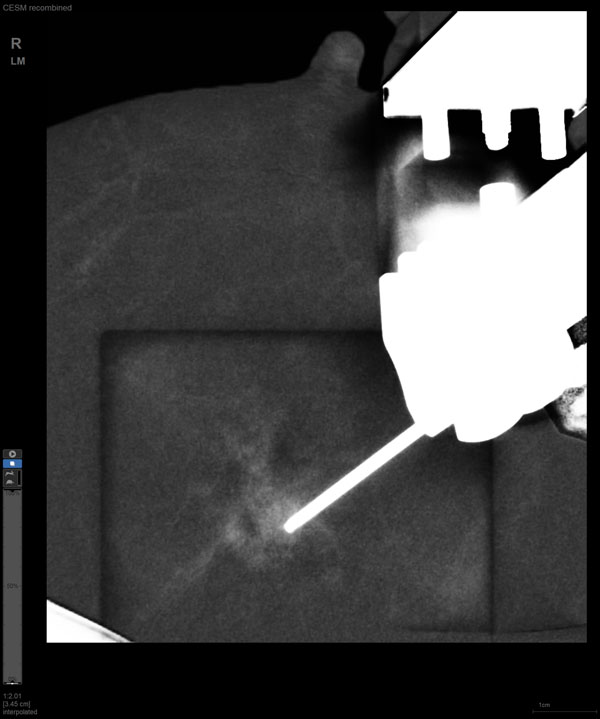

近日,我院放射科成功开展首例“乳腺对比增强X线摄影(contrast-enhanced mammography, CEM)引导下穿刺活检术”。该技术定位精准、安全微创、简便快捷、舒适经济,通过对穿刺获得的肿物组织标本进行病理检查,为临床后续治疗提供科学依据,为乳腺癌患者早诊早治带来新的福音。

CEM引导下穿刺

某患者增强磁共振成像MRI显示肿瘤周边有活性,中心区域有组织坏死。为得到准确的病理结果,穿刺靶区需避开肿物坏死区域。在与患者主管医生充分讨论后,放射科医生为患者行CEM引导下穿刺活检术。术中,CEM检查肿物同样显示为环形强化,巧妙避开坏死区域后,穿刺靶区选择了肿物增强早期明显强化区域,术程顺利,仅用时15分钟。术后该患者病理结果为浸润性导管癌Ⅱ级。

国内首台具有数字乳腺断层摄影(DBT)和CEM引导下穿刺功能的X线机